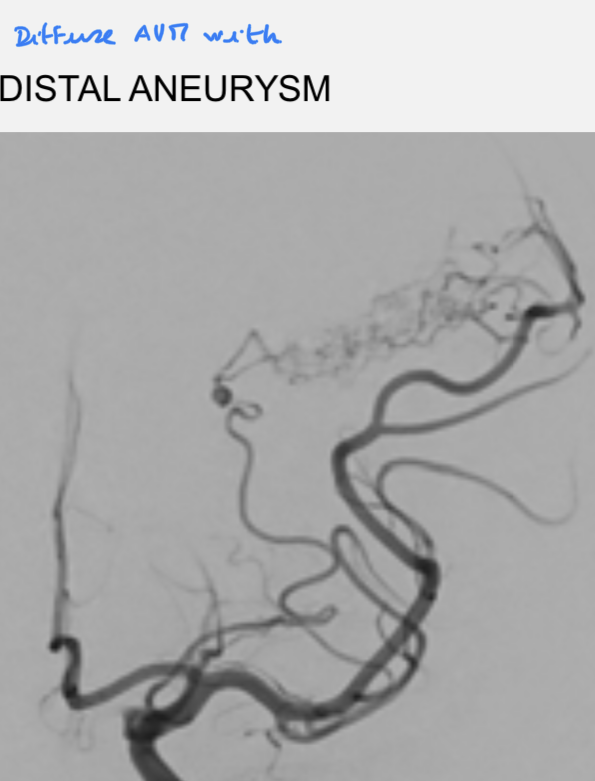

AVM:

AVM - nidus:

AVM - ddx